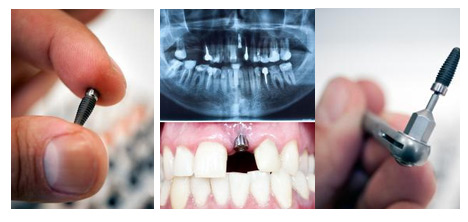

一颗好的种植牙基本可以用40年(护理得当情况下),这颗牙基本可以让您一辈子使用。种植牙不仅在寿命和功能上深受顾客关注和追捧,种植价格上也成为缺牙顾客考虑的重点,下面和康贝佳口腔医院的医师一起来看一下种植牙的具体价格。

种植牙是按颗数算的,有的人缺了1颗,有的顾客缺了半口牙,没确定自己要做几颗前,医生无法根据个人口腔情况给出参考价格。而康贝佳的all-on-4种植牙,更能以4颗种植牙恢复整整半口牙。

不同种植体的品牌价格相差其实很大,还有国产和进口之分,有些医院将种植牙的价格开得很低就是这个道理。康贝佳口腔对于引进的种植体有着非常严格的筛选,全面保障顾客选用种植体的安全及品质。

三、确定价格第三步,选择合适的牙冠

如果是修复后牙,那选择钴铬合金烤瓷牙和全瓷牙就够了,如果是修复前牙,那还是选择全瓷牙吧,因为全瓷牙外观比较接近真牙,不会影响美观。